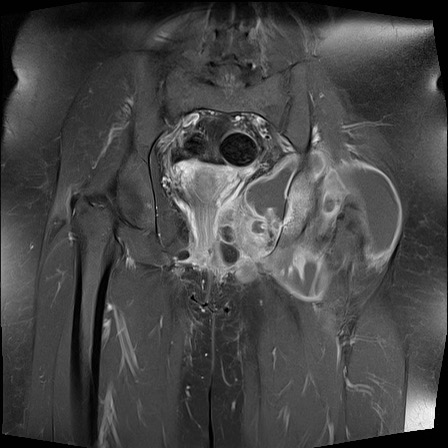

Hình ảnh X-quang khung chậu của bệnh nhân viêm khớp do lao tại khớp háng trái.

Có hẹp khe khớp kín đáo kèm theo xơ cứng dưới sụn tại khớp háng trái.

Các dấu hiệu X-quang này không đặc hiệu và rất có thể là biểu hiện của thoái hóa khớp.

Tiếp tục xem hình ảnh MRI…

Điều bất ngờ với tất cả mọi người là có nhiều ổ áp-xe.

Khi hình thành áp-xe lan rộng như vậy trong khi biểu hiện lâm sàng lại tối thiểu, cần luôn nghĩ đến viêm khớp do lao.

Chẩn đoán viêm khớp do lao được xác lập bằng chọc hút dịch khớp.